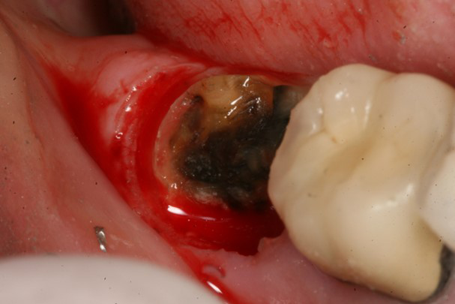

Figure 1 shows an example of a deep subgingival margin with the ensuing bleeding. If we are planning on packing a cord, we need to pack multiple cords soaked in hemostatic agent and wait for the soft tissue to move away from the tooth margin and achieve hemostasis. We have all experienced the moment of truth when the cord is removed, which oftentimes reinitiates the bleeding and the soft tissue again flops over the tooth margin, making it almost impossible to get an adequate impression the first time. This results in the loss of time, incurred cost of another tray full of material and the patient needing to undergo a mouthful of gagging material.

Compare this to use of the Gemini laser. We can set the power setting of the laser using the preset power settings for “Troughing” (Fig. 2) at 1.1 watts. The pre-initiated tip (pigment on the laser fiber converts some of the laser energy to photothermal energy) is placed into the sulcus to ablate the soft tissue, which creates a clear separation of the soft tissue from the tooth margin and achieves instant hemostasis (Fig. 3). We then have no need to wait and can immediately take the impression (Fig. 4). I consider this alone as priceless in my day-to-day practice.

Fig. 1 Fig. 2 Fig. 3